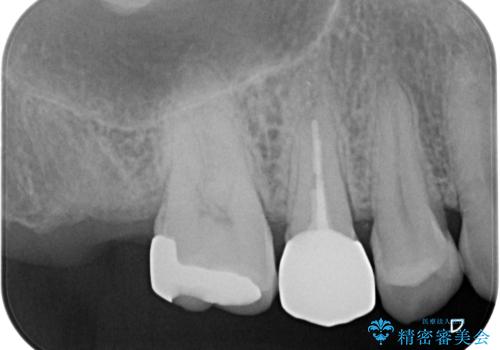

顕微鏡を用いて根管治療を行うことで、破折の有無などを判断しやすくなります。

- 右上の歯が、噛むと痛いことを主訴に来院されました。

ラバーダムと顕微鏡を用いた根管治療を希望され、治療後は痛みも改善することができました。